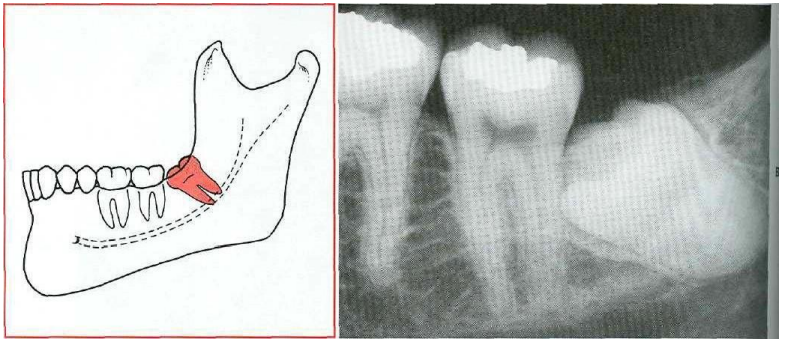

4-Vertical 14.

Vertical impaction the long axis of the impacted tooth runs in the same direction as the long axis of the second molar

Fig 4: Vertical impaction "Contemporary Oral and Maxillofacial Surgery, chapter 9.Larry J. Peterson. Principles of management of impacted tooth p 195.